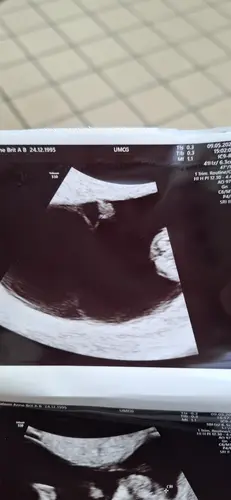

Vandaag de 2e echo gehad. 10 dagen geleden de 1ste en daar zagen we alleen 2 dooierzakjes. Vandaag 2 sterk kloppende hartjes en mini frummeltjes van 7.6 en 8.1 mm 馃┑馃┓

Vind het zo bijzonder en spannend tegelijkertijd